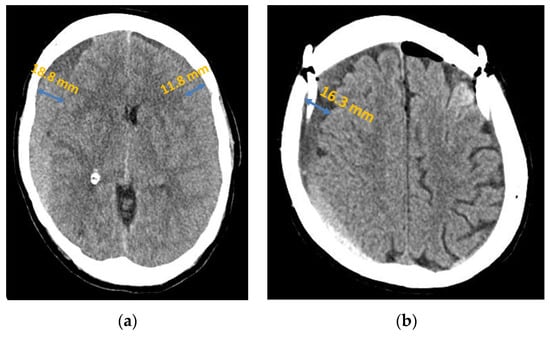

Width

In the patient group with a recurrence, the mean haematoma width was 22.83 mm (±1.31), whereas in the group without recurrence, it was 16.23 mm (±0.73). The t-test yielded a p-value of 0.000007, which showed that increasing haematoma size was statistically significantly related to the increased probability of recurrence of a chronic subdural haematoma. Table 2 shows an example of the statistical analysis of the data, in this case in relation to haematoma width.

Our study showed a statistically significant difference in the mean value of the haematoma width measured in the axial plane at the punctum maximum. These results are consistent with some of the studies in the literature [35]. This is primarily attributed to the greater displacement of brain parenchyma and the correspondingly greater necessary re-expansion of brain after haematoma relief [23]. On the other hand, in a study by Huang, Lin et al., there was no significant correlation between haematoma size and recurrence rate in the patient collective [36]. Due to these inconsistent findings, further studies with standardised volume calculation or size determination are required in order to clearly define the correlation.